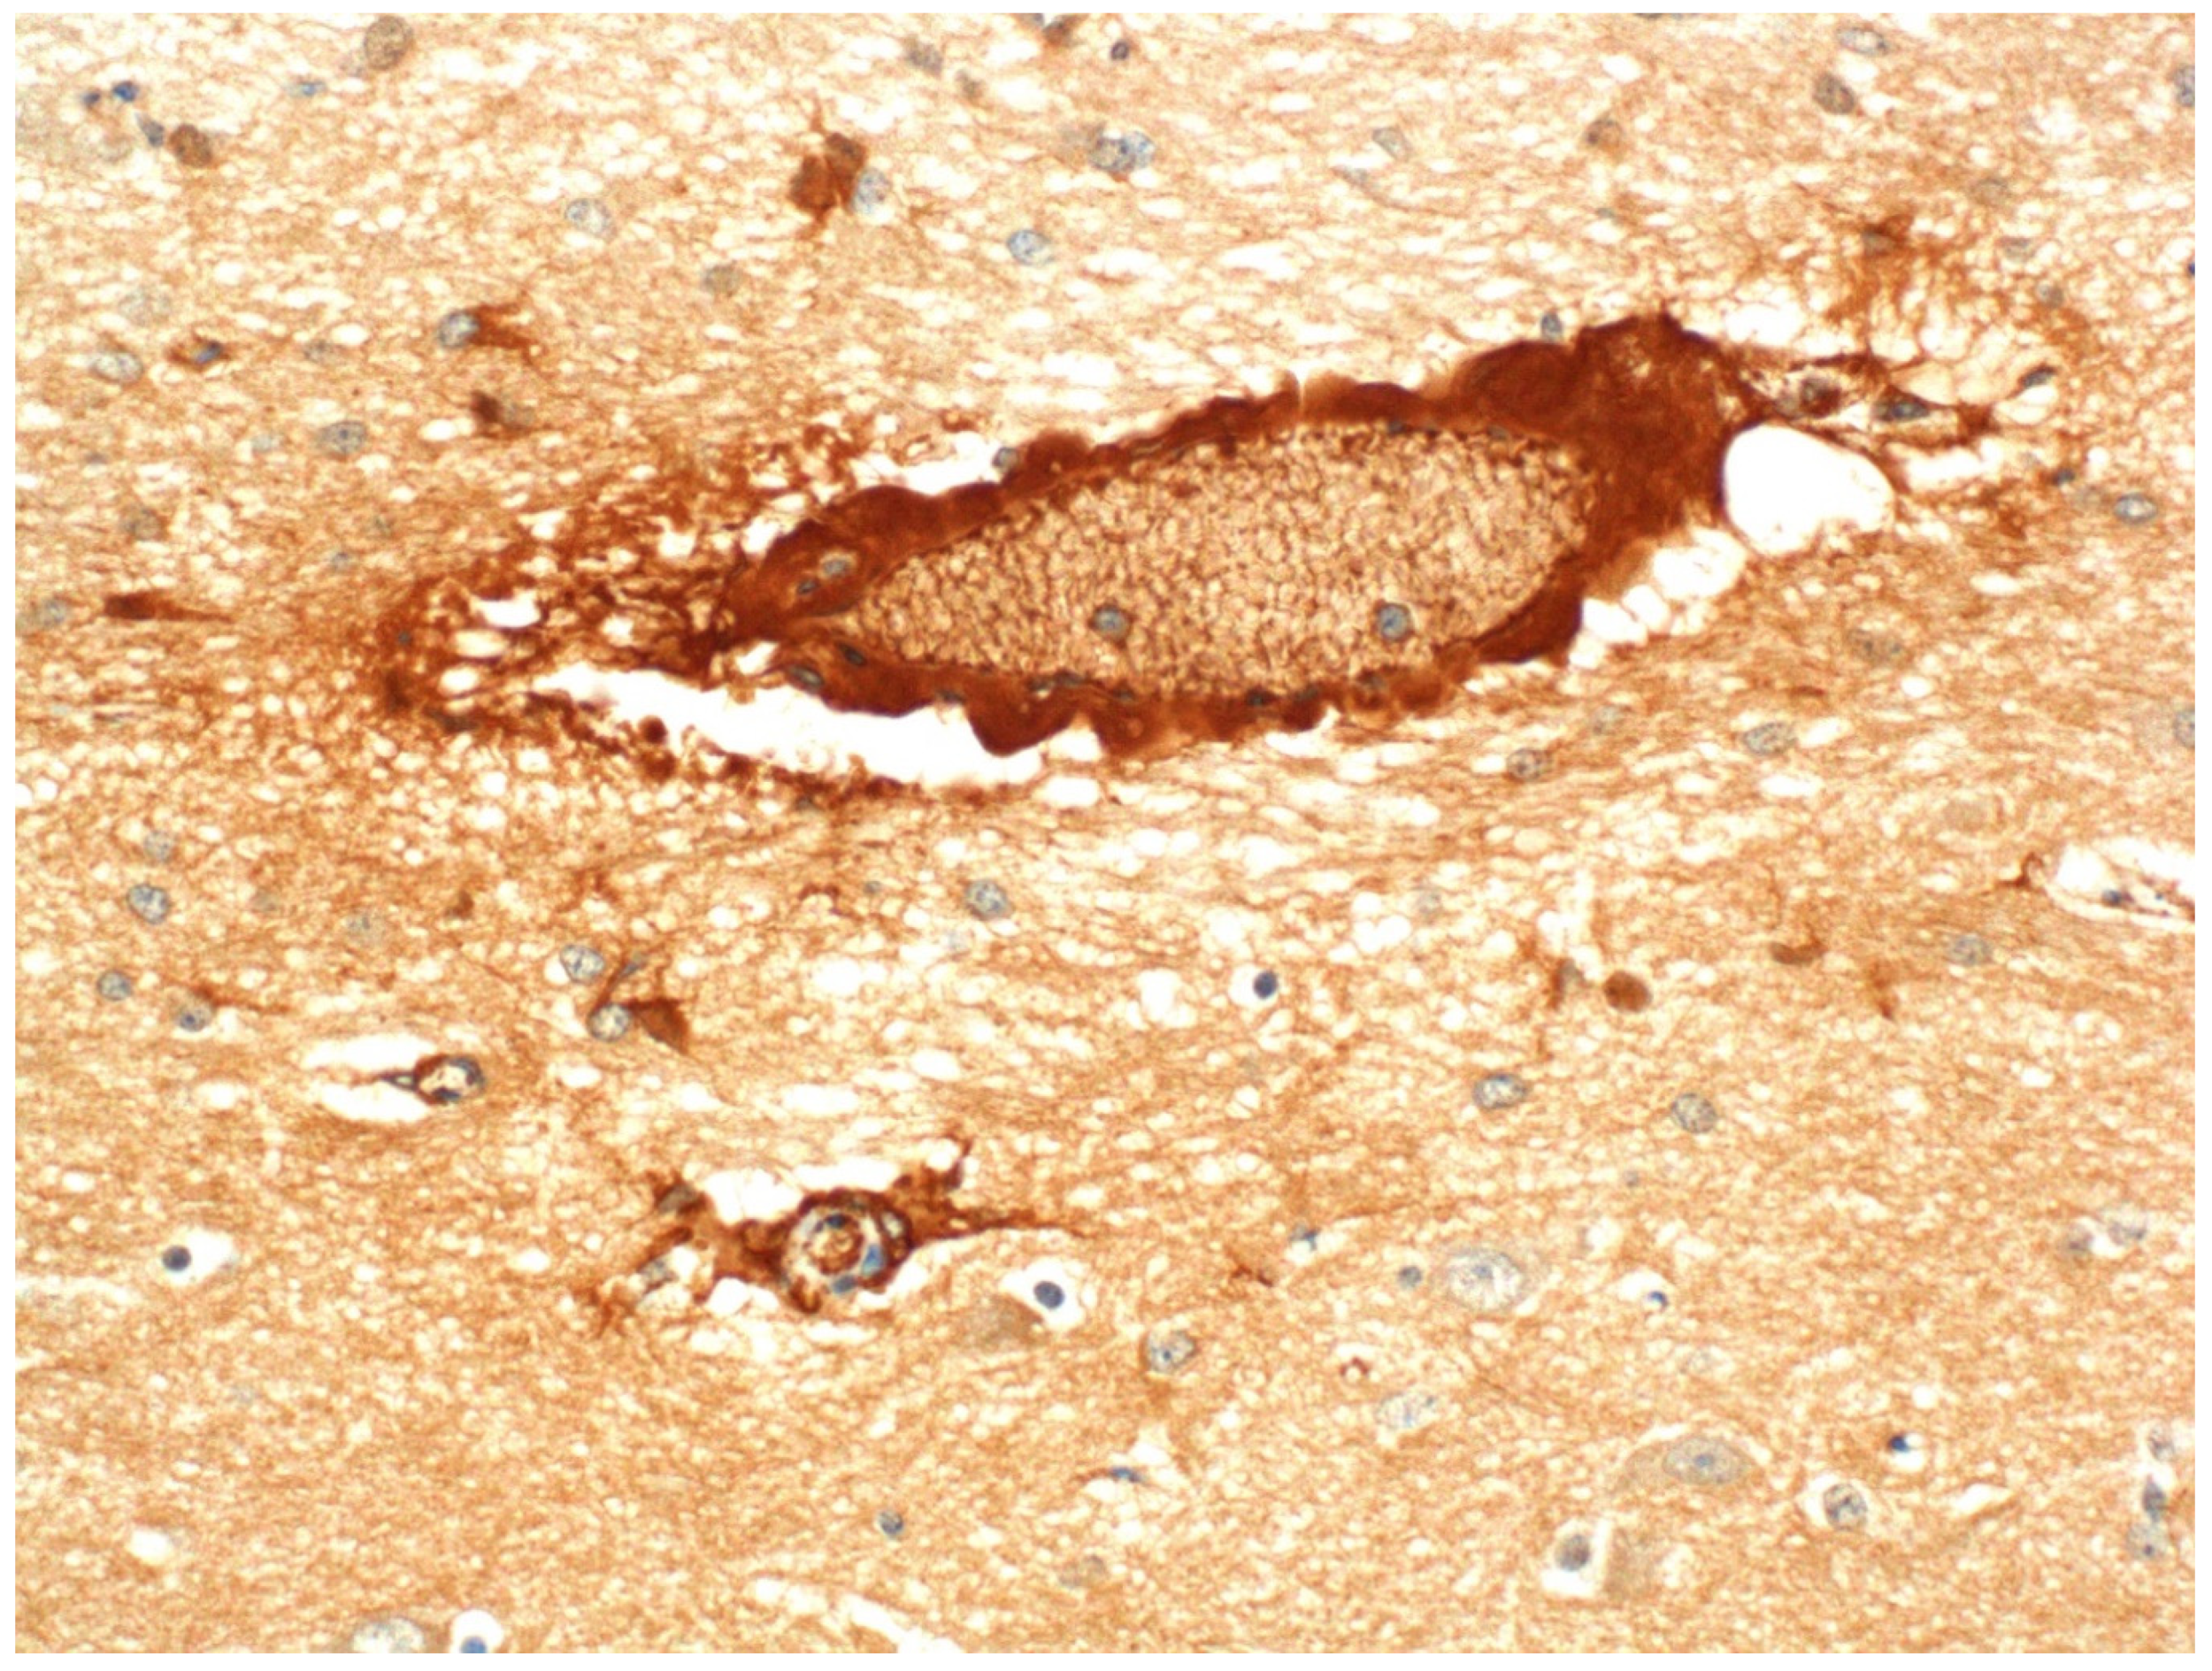

- Finnie, J.W.; Hajduk, P. An immunohistochemical study of plasma albumin extravasation in the brain of mice after the administration of Clostridium perfringens type D epsilon toxin. Aust. Vet. J. 1992, 69, 261–262. [Google Scholar] [CrossRef] [PubMed]

- Finnie, J.W.; Manavis, J.; Chidlow, G. Loss of endothelial barrier antigen (EBA) immunoreactivity as a marker of Clostridium perfringens type D epsilon toxin-induced microvascular damage in rat brain. J. Comp. Pathol. 2014, 151, 153–156. [Google Scholar] [CrossRef]

- Manavis, J.; Blumbergs, P.; Jerrett, I.; Hanshaw, D.; Uzal, F.; Finnie, J. Heterogeneous immunoreactivity of axonal spheroids in focal symmetrical encephalomalacia produced by Clostridium perfringens type D epsilon toxin in sheep. Vet. Pathol. 2022, 59, 328–332. [Google Scholar] [CrossRef]